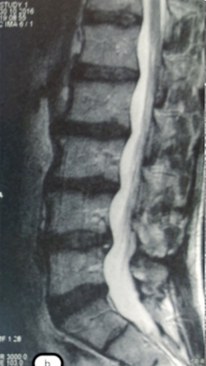

Спондилодисцит L3 – L4

4 процедуры ФДТ, 9 процедур MBST, 20 процедур ИПМТ

Параметры изменяются в зависимости от процедуры

Дата публикации: 22.08.2025 14:27:12